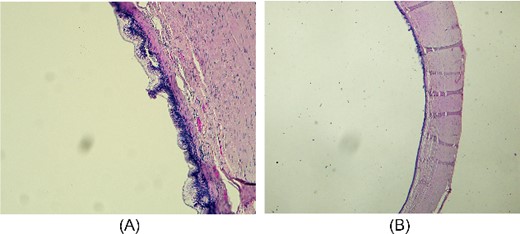

The resected specimen consisted of 8-cm-long appendix with enlarged lumen, comprising a cystic neoformation with a maximum diameter of 1.8 cm and mucinous content, partially disepithelized and sometimes flattened mucinous and cubic epithelial lining, in the absence of atypia. A chronic lymphocytic inflammatory infiltrate of the bowel wall was associated. The caecum resection margin was free of disease. Histopathological findings were compatible with the diagnosis of LAMN according to the International Modified Delphi Consensus Process classification [7] (Fig. 5A–B). At 6-month follow-up, the patient resulted in good condition.

Microscopic appearance of mucinous cystadenoma of the appendix. (A) Proliferative and partially papillary configuration of the mucosa; haematoxylin and eosin, magnification ×20. (B) Evidence of flattened mucosa accompanied by atrophy, fibrosis and chronic inflammation of the underlying wall; haematoxylin and eosin, magnification ×10.